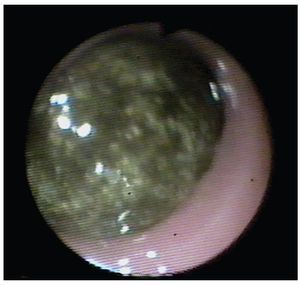

Se trata de paciente femenino de 75 años de edad, la cual acude al servicio de urgencias por presencia de vómitos en varias ocasiones de contenido gástrico, intolerancia a los alimentos, malestar generalizado y datos francos de deshidratación secundaria, con 15 días de evolución desde el inicio de su padecimiento. La paciente tiene antecedentes de diabetes mellitus, hipertensión arterial y refiere gastritis crónica en tratamiento. A su ingreso se encuentra orientada, conciente y sin datos de alarma abdominal, por lo que es internada para su estudio y estabilización con sospecha de cuadro de estenosis péptica pilórica. Se coloca sonda nasogástrica drenando aproximadamente 3 L de material gástrico espeso y restos de alimentos. Laboratorios a su ingreso con hemoglobina de 10 mg/dL, leucocitosis de 13,000 mm3, glucosa 96 mg/dL, urea 30 mg/dL, creatinina 1.8 mg/ dL. Una vez con la paciente en mejores condiciones, se decide realizar panendoscopia encontrando un cálculo biliar gigante impactado en el bulbo duodenal (Imágenes 1 y 2) realizándose múltiples maniobras de extracción con pinzas de cuerpo extraño, las cuales no fueron exitosas. Se realizó ultrasonido demostrando la presencia del cálculo impactado en duodeno, no se apreció dilatación de vías biliares (Imagen 3). Con estos hallazgos se decide someter a la paciente a cirugía, encontrando la presencia de un cálculo biliar gigante dentro del bulbo duodenal con vesícula biliar escleroatrófica, se realiza duodenotomía y extracción del cálculo con duodenorrafia en 2 planos tipo Heineken-Mikulicz sin incidentes transoperatorios (Imágenes 4, 5 y 6) y con adecuada evolución, siendo egresada al octavo día del posoperatorio.

Imagen 5. Duodenorrafia en 2 planos tipo Heineken-Mickulicz y parche de epiplón.

Imagen 6. Cálculo una vez extraído.